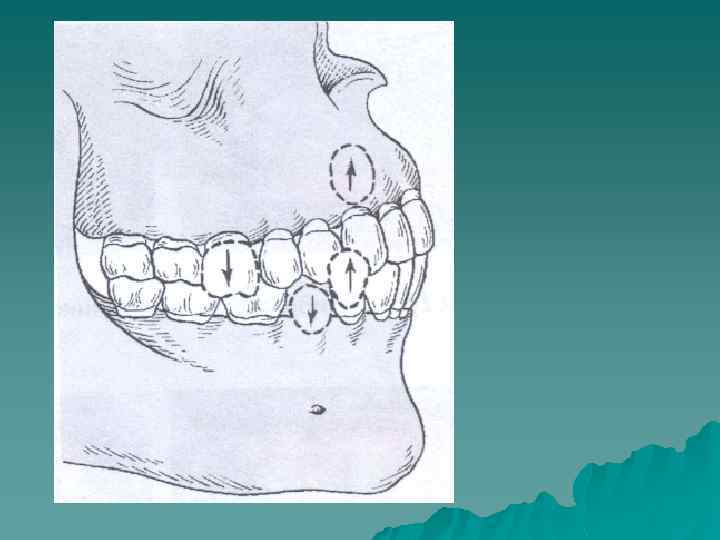

Зубы могут занимать неправильное положение в пределах зубного ряда или располагаться вне его. Соответственно трем взаимно перпендикулярным направлениям выделяют шесть основных видов неправильного положения зубов четыре в горизонтальном и два - в вертикальном направлениях.

Соответственно различают u вестибулярное u оральное u дистальное u мезиальное положение зубов u супраположение u инфраположение, u тортоаномалию u транспозицию зубов

Аномалии положения зубов по вертикали Различают супраположение, инфраположение Супраположение - это смещение зуба в вертикальном направлении, когда зуб находится выше окклюзионной кривой. Причины: отсутствие зубов-антагонистов на верхней челюсти, неполное прорезывание зубов на верхней челюсти, чрезмерный рост альвеолярного отростка на нижней челюсти и недоразвитие его на верхней челюсти. Диагностируют при осмотре рта. Степень смещения устанавливают относительно окклюзионной плоскости. Наиболее информативен метод телерентгенографии.

Инфраположенuе - смещение зуба в вертикальном направлении, когда зуб находится ниже окклюзионной кривой. Причины: отсутствие зуба-антагониста на нижней челюсти, неполное прорезывание зубов на нижней челюсти, чрезмерный рост альвеолярного отростка на верхней челюсти и недоразвитие его на нижней челюсти